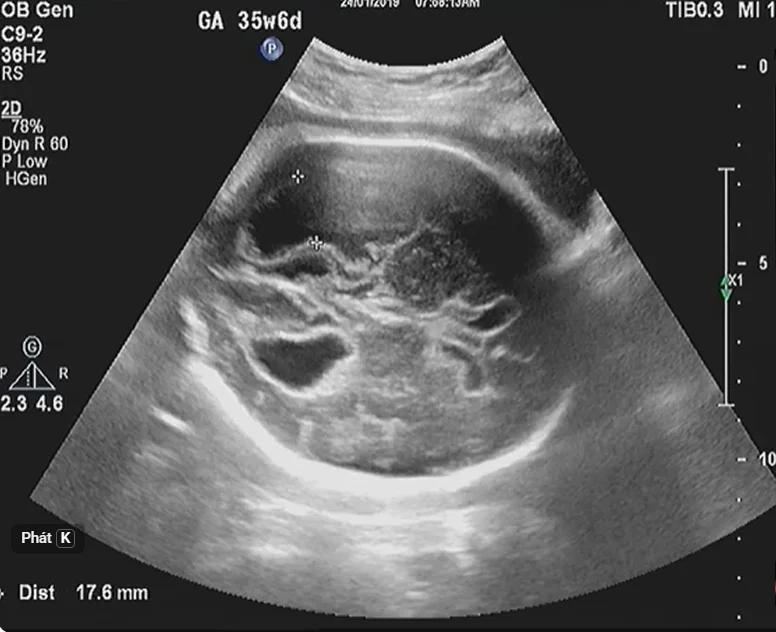

Nhiễm trùng Toxoplasma bào thai

01/04/2026